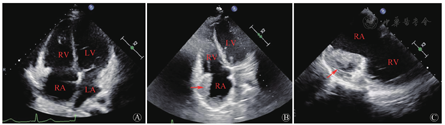

患者行TEE提示右心房及心包内可见多处中低回声团块影,最大位于近右房室沟,大小约49 mm×25 mm,其内血流丰富,并再次观察TTE,在非标准切面显示右房占位(图2)。考虑肿瘤性病变可能性大。胸部增强CT见右心部分心包增厚,右心房、房间隔多发富血供占位,部分明显强化,部分成分强化不明显,不除外血栓形成(图3)。PET/CT躯干断层显像:右心房增大,形态欠规则,密度不均匀,右心房、右心室及相邻心包脂肪间隙代谢不均匀异常增高,SUVmax 11.9,不除外恶性病变可能;T2椎体左后方肌间隙代谢增高灶,SUVmax 5.3,性质待定。颈胸椎旁肌肉MR增强及DWI成像均未见异常。

RV:右心室;LV:左心室;RA:右心房;LA:左心房。A:体表超声:标准心尖四腔心切面,右心房占位不明显;B:体表超声:非标准四腔心切面,可见右心房靠近房室沟部位团块性占位(箭头所示);C:TEE:非标准右心切面,可见右心房占位,其内回声不均匀(箭头所示)